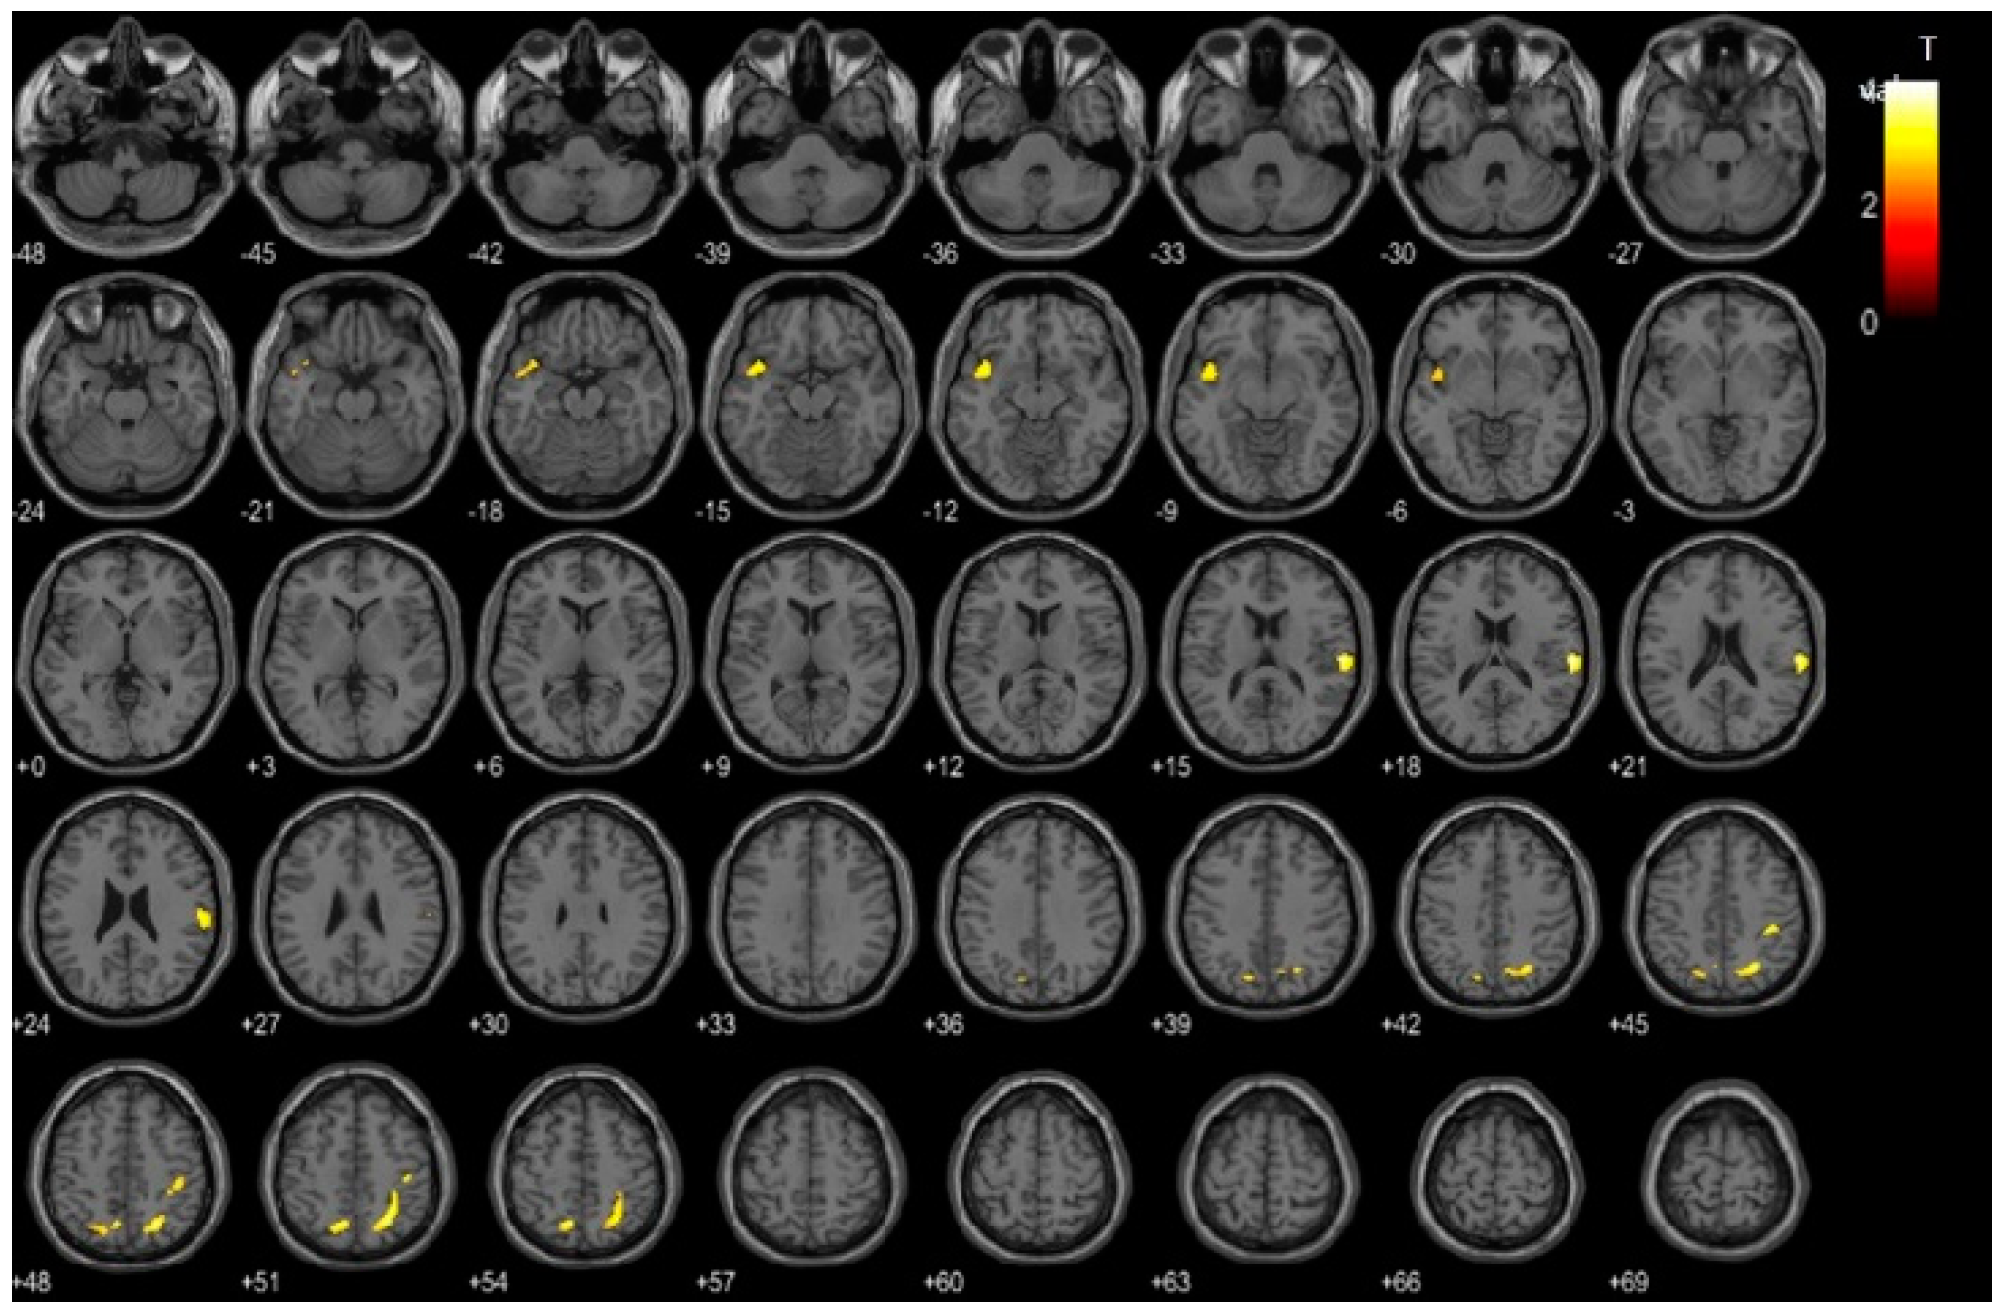

Cerebral glucose metabolism was compared between the high- and low-VAT-metabolism groups based on voxel-wise analysis using statistical parametric mapping (SPM). This analysis revealed significantly decreased cerebral glucose metabolism in the high-VAT-metabolism group compared to the low-VAT-metabolism group across the bilateral parietal and temporal cortices (Figure 2). Table 2 shows the specific brain regions in which the high-VAT-metabolism group exhibited decreased cerebral glucose metabolism relative to the low-VAT-metabolism group.

Figure 2.

Voxel-based comparison of cerebral glucose metabolism between the high- and low-visceral adipose tissue (VAT)-metabolism groups. The statistical parameter mapping t-maps were su-perimposed on the volume-rendered magnetic resonance imaging (MRI) and T1-weighted template in the axial plane for the high-VAT-metabolism group < low-VAT-metabolism group (p < 0.005, uncorrected at voxel level, cluster size > 100 voxels).